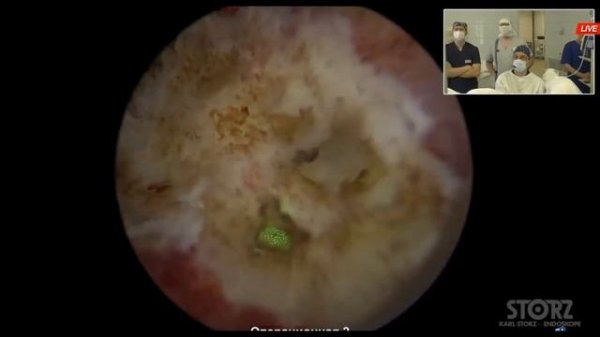

Мастер-класс «Лазерная энуклеация аденомы простаты» - лазер FiberLase U3 (Сорокин Н.И.)

Лазерная энуклеация гиперплазии предстательной железы, Дымов А.М. Фрагмент операции, Челябинск, 2022

Конференция «LIVE SURGERY. Лазерные технологии в урологии» (Челябинск, 24.06.2022г.)